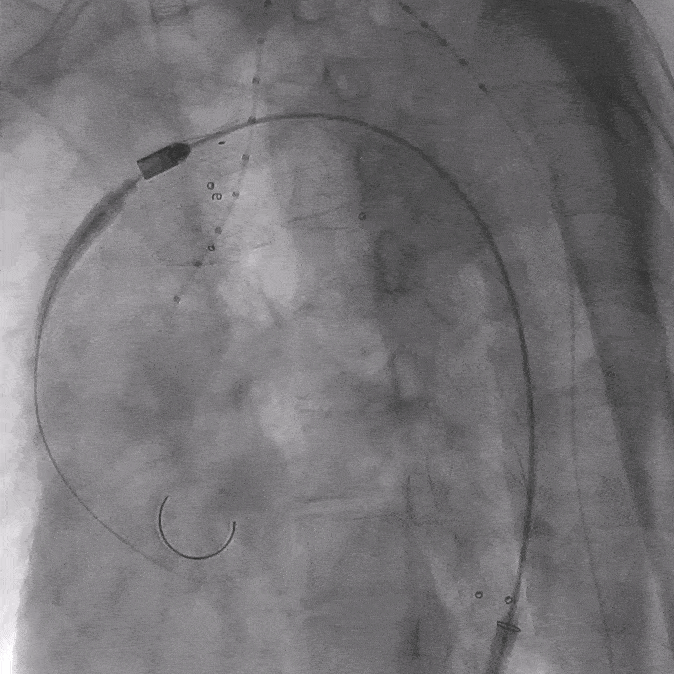

05. 0.035″长泥鳅导丝进一步超选进入降主动脉段,并沿右股动脉引入抓捕器抓取泥鳅导丝建立导丝路径,依次逐级使用4*40mm、6*40mm、8*40mm Amanda球囊扩张破膜处。期间可见明显受压切迹影。

06. 沿右股动脉引入8F长鞘,置入8*50mm Viabahn覆膜支架于开窗处,远端避开左椎动脉,近端超过覆膜支架1cm并完成释放。

07. 最后行全主动脉造影示LSA开窗支架重建良好,近端主体支架定位显影良好,腹主动脉右肾动脉、腹腔干动脉及肠系膜上动脉显影较支架植入前明显改善。

08. 撤出各导丝、导管、鞘管,收紧预埋缝合线,加压包扎各穿刺点。术毕。术后无相关不良并发症。

术后1周复查主动脉CTA显示胸主动脉血管重塑良好,开窗支架形态正常。远端内脏区显影良好。